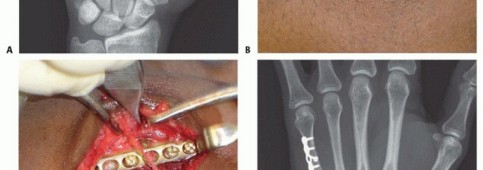

FIG 3 • A. Fracture of the neck of the fifth metacarpal with a flexed, apex dorsal angulation (boxer's fracture). B. Torsional injuries lead to long oblique fractures with a risk for malrotation. C. Short transverse fracture from a direct impact. D. Crush injuries can lead to a combination of injuries with an increased risk of compartment syndrome and significant stiffness. The shortened fourth metacarpal pulls the head of third metacarpal in a proximal and ulnar direction through deep transverse metacarpal ligament. E. Neglected fight bite injury ultimately leading to loss of the metacarpal head. Crush injuries can lead to comminuted fractures with significant soft tissue injuries and a heightened risk of compartment syndrome (FIG 3D).

History: Note the mechanism of injury, time since injury, and any treatment received so far. Also, note the age, vocation, and hobbies of the patient. Comorbidities should also be recorded.Inspection: The skin needs to be checked for any signs of an open fracture. A small laceration near the MP joint may be the only sign of a “fight bite” injury which requires urgent débridement to prevent joint and bone infection (FIG 3E). Also, note digit malrotation and extension lag at the MP and proximal interphalangeal (PIP) joints. A severely edematous hand may signal compartment syndrome or an internal degloving injury.Palpation: The neurovascular examination should include checking activation of the first dorsal interosseous muscle to confirm activity of the motor branch of the ulnar nerve. Tense compartments and pain with passive motion may signal a developing compartment syndrome.